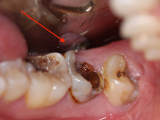

RĂNG SÂU NẶNG CÓ BỌC SỨ ĐƯỢC KHÔNG ?

Sâu răng là bệnh lý răng miệng phổ biến, không chỉ gây đau đớn, ảnh hưởng đến chức năng ăn, nhai mà sâu răng còn gây mất thẩm mỹ cho người bệnh.

Sâu răng là một trong những tình trạng răng miệng phổ biến nhất hiện nay. Ai trong số chúng ta cũng đã và đang có một hoặc vài chiếc răng bị sâu. Nguyên nhân chủ yếu là do không chăm sóc răng miệng thường xuyên, khiến mảnh vụn thức ăn tích tụ thành mảng bám và tạo điều kiện vi khuẩn phát triển.